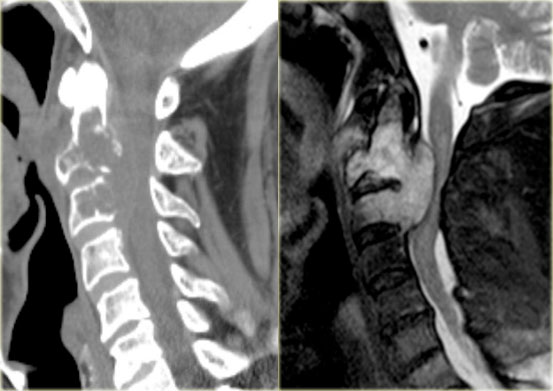

Here images of a patient with lytic lesions of the C2 and C3 vertebrae with cortical destruction posteriorly.

The differential diagnosis based on the CT-findings includes primarily metastases and myeloma.

The sagittal T2-weighted image with fat saturation demonstrates continuity between the abnormalities with soft tissue extension and compression of the myelum.

Now our differential should also include chordoma which has its origin in the neural axis as it arises from notochord remnants.

Chordoma (2)

Here another case of the cervical spine.

T2 weighted images with and without fat suppression.

Notice the involvement of more than one vertebral level, extensive soft tissue mass and very high signal intensity.